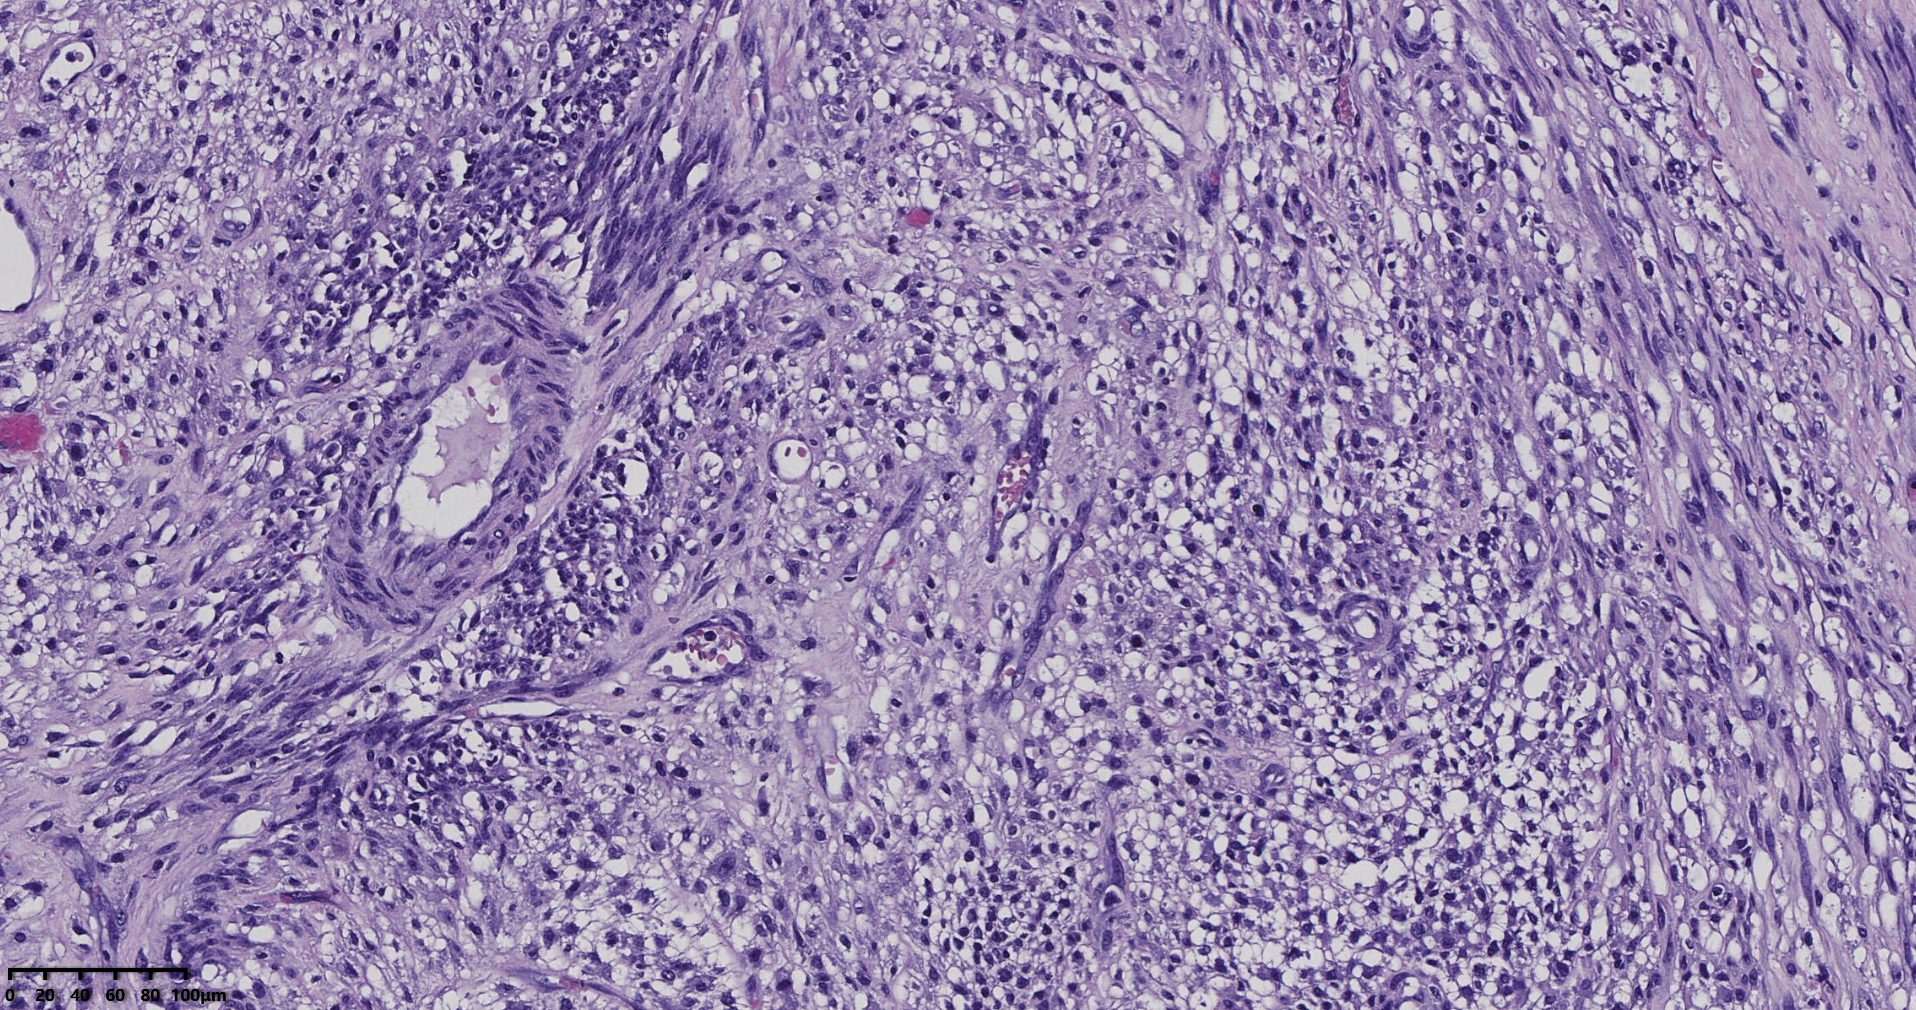

送检灰白肿物十余个,直径多在2-3厘米,切面均为灰白、实性,质地韧,其中一个大肿物,直径约7厘米,切片灰白灰红,质地韧当时取材时印象还是平滑肌瘤,伴变性,不考虑肉瘤,因为形态规整,质地韧,不脆,切面灰白,不是灰黄。

镜下所见小肿物无特殊,大肿物瘤细胞密集,中心区有变性、坏死,瘤细胞核有异型性。大肿物补充取材,发现,部分区域切面灰黄,这个区域,瘤细胞更密集,异型性更显著。肿物边缘有薄层正常平滑肌组织被覆,靠近边缘瘤细胞最密集,局部瘤组织内小血管较丰富。

会诊:考虑平滑肌肉瘤。

北医三院会诊:子宫平滑肌瘤伴红色变性可能性大,建议加做免疫组化及NGS检测进一步明确诊断。